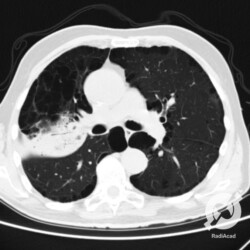

Os agentes etiológicos infecciosos são variados (bactérias, vírus, fungos, parasitas…), mas o que ocorre nos pulmões durante uma infecção por qualquer tipo de agente é a substituição do ar alveolar por secreção (pus, muco, eventualmente sangue ou necrose…) e com isso a manifestação radiográfica vai ser a mesma já que todas estas secreções apresentam a mesma densidade radiográfica: partes moles.

E o nome dado a esta alteração radiográfica que corresponde à substituição do ar alveolar por líquido é a consolidação alveolar.

Uma consolidação alveolar é, por definição, uma opacidade (imagem densa, branquinha) homogênea ou às vezes heterogênea (pela presença de calcificações ou cavidades), de limites mal definidos, exceto quando toca a pleura da parede ou das cissuras pulmonares. É um termo usado tanto em radiografia, como em tomografia computadorizada. Na tomografia, um outro termo é usado: vidro fosco, que é uma opacidade (branquinha mas não tanto como a consolidação), que borra o pulmão mas deixa ver os vasos de permeio (igual bigode de adolescente: dá pra ver todo o fundo).

Nós vamos mostrar aqui um pequeno apanhado de pneumonias de variados agentes, em diversos segmentos e lobos pulmonares, com extensões variadas. O objetivo é identificar o padrão radiológico de consolidação alveolar e não determinar o agente infeccioso, isso vai ser assunto para mais adiante. Aliás já antecipo que é fundamental saber localizar a lesão, porque alguns destes bichos gostam de determinados segmentos, alguns tumores também têm as suas preferências, então localização é fundamental. Se localização não fosse importante, um apartamento na beira do mar sairia o mesmo preço de um apartamento de frente pra BR-101, concordam?